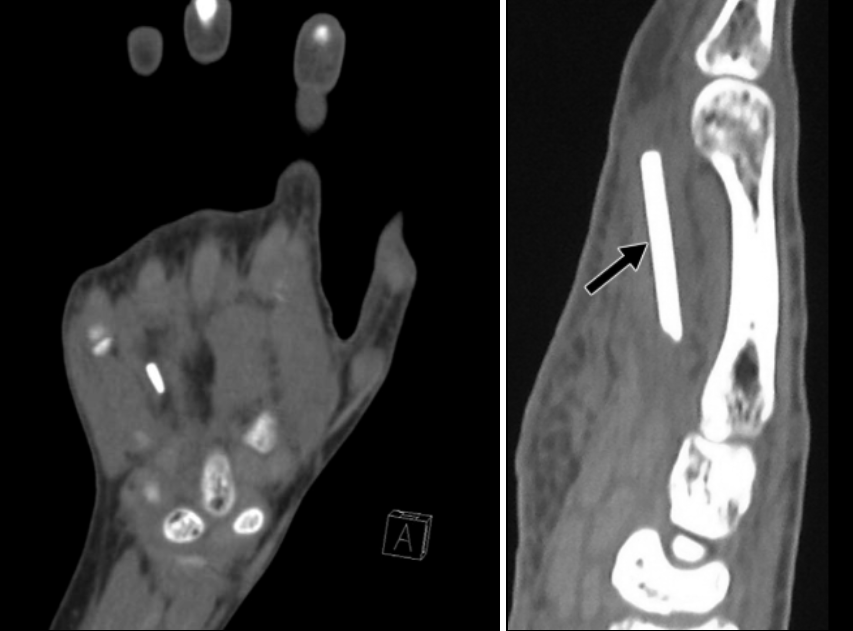

단순 X-ray로 금속, 유리 등 고밀도 이물질은 대부분 확인 가능하며, 나무나 식물성 이물질은 명확히 드러나지 않을 수 있으므로 초음파 검사나 CT가 유용합니다.

비교적 큰 덩어리의 유리 파편

쇠조각

초음파상 굴곡건 표층으로 이물질 확인

CT소견상 정확한 위치등을 파악하기 좋음

상처부위 주변 조직의 부종, 감염 소견을 함께 평가합니다.